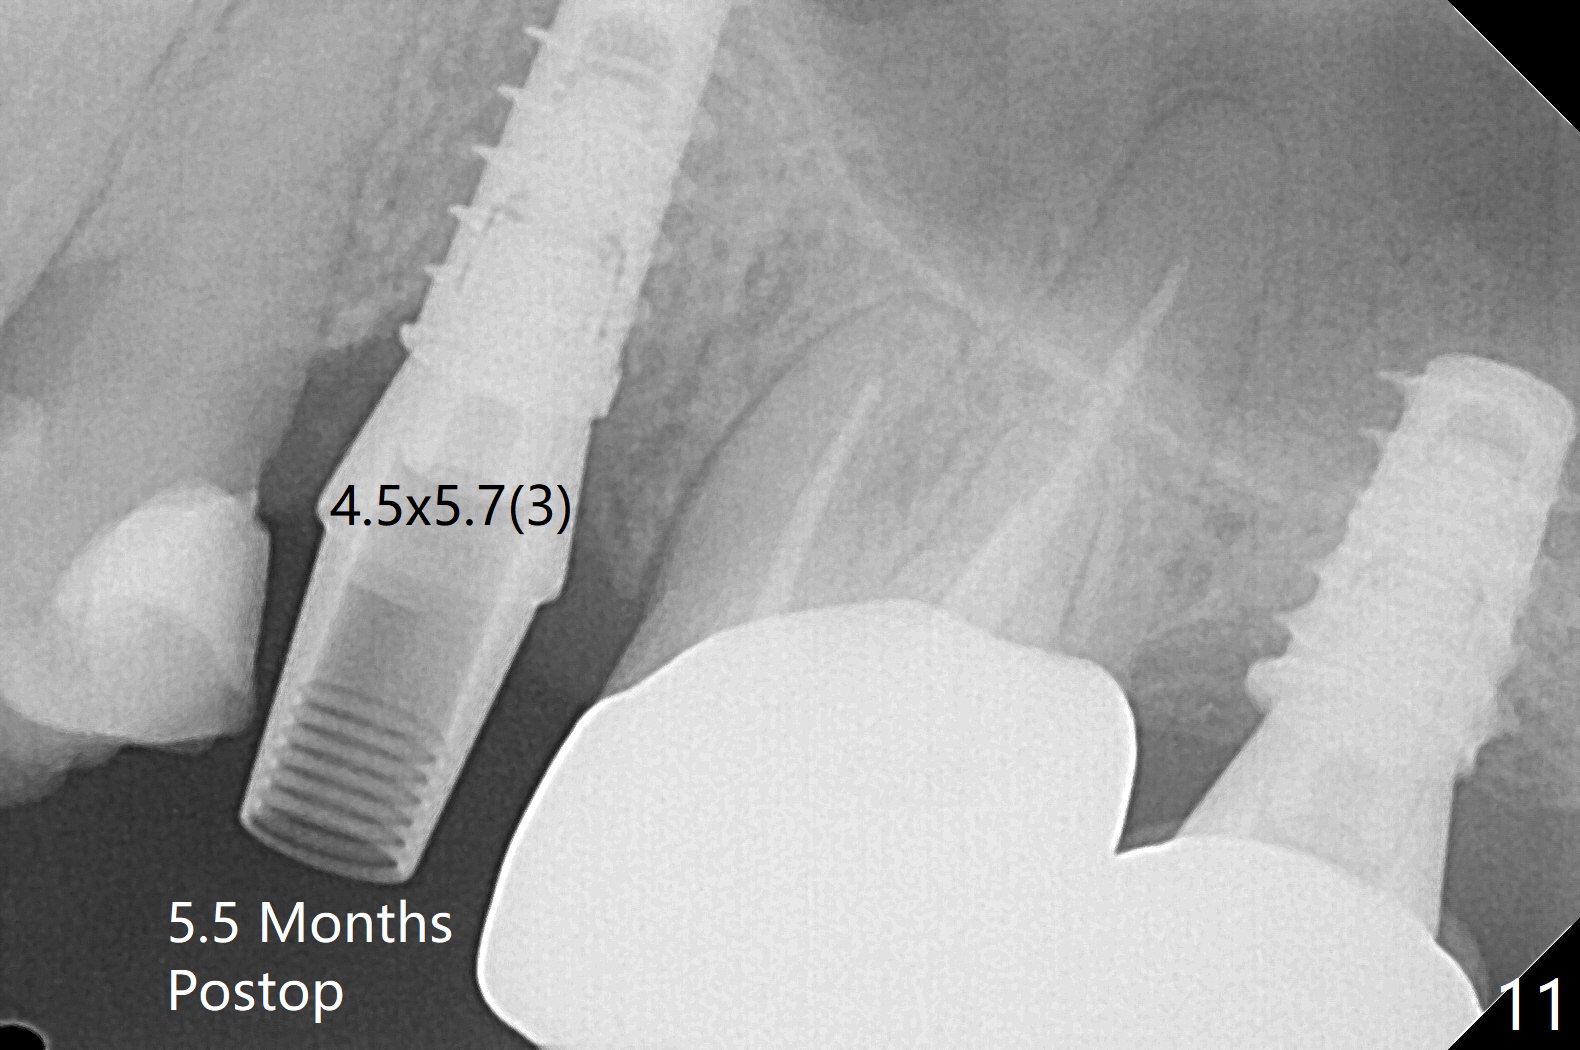

The patient with the anterior cross bite at the left lateral and canine and incipient Class V caries returns to clinic for #13 residual root extraction (Fig.1,2). There is no quality root structure (Fig.2) or space (Fig.3) for socket sheath. Two amalgam carriers of Vanilla is inserted and pushed by the 4x11 mm dummy implant for sinus lift (Fig.4 *). When the same sized final implant (4x11 mm) is placed, a 5.5 mm bone profile drill is used to trim the proximal crests (Fig.5 * sticky bone packed in the buccal and palatal gaps). In fact the implant turns when a 4.5x4(3) mm pair abutment is tightened. The implant is backed up; with a healing screw, sticky bone is placed (Fig.6 *) and then covered with a piece of PRF and a part of GEM cap. The wound is sutured with 4-0 PGA; periodontal dressing is applied. The implant is somewhat over-seated without the bone graft covering the apical end of the implant (Fig.7, as compared to Fig.4). A 4.5 mm implant should be placed. The GEM Cap appears to be absent 9 days postop, while the periodontal dressing dislodged in 1 week (Fig.8). It appears that the existing abutment at #15 is incompletely seated (Fig.3, 5.5x4(2) mm). After use of 5.5 and 6.0 mm bone profile drills, a 5x4(3) mm abutment is placed with 35 Ncm torque. In fact the bone graft coronal to the implant remains (Fig.9 *) in spite of apparent loss of the overlying PRF and GEM cap (Fig.8). After use of a 4.6 mm profile drill, a 5.5x3 mm healing abutment is placed 4.5 months postop (Fig.10). Without a provisional at #13 for ~ 4 months, there is a gap between crowns at #14 and 15 (not shown due to angulation). Impression is taken for #13 crown fabrication 5.5 months postop and for #15 crown repair (addition of porcelain for the mesial contact, Fig.11). It appears critical for a provisional to maintain the position of the neighboring tooth.